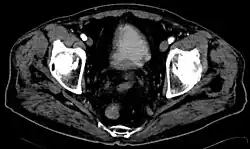

Balkenblase (Trabekelblase, (Pseudo)divertikelblase) ist ein Fachausdruck aus der Medizin. Man bezeichnet damit eine Veränderung der Harnblase, die bei erschwerter Harnentleerung auftritt. Es kommt zu einer balkenartigen Verdickung (Hypertrophie) der Muskulatur, zu einer unregelmäßigen Innenkontur und wahrscheinlich auch zum vermehrten Auftreten von Harnblasendivertikeln. Die Blase ist in diesem Zustand nicht mehr voll kontraktionsfähig.

Besonders häufig tritt die Balkenblase bei Männern auf, deren Prostata sich mit zunehmendem Alter vergrößert und die Harnröhre abdrückt. Da dieser Vorgang langsam über Monate und Jahre abläuft, hat die Harnblase Zeit, sich durch eine Verstärkung der Muskulatur darauf einzustellen. Meist wird dieser Vorgang nicht bemerkt, da er keine Schmerzen bereitet und die Harnentleerung nur etwas verlangsamt ist. Erst wenn andere Probleme, wie eine Restharnbildung und vermehrte Harnwegsinfekte oder ein Nierenaufstau dazukommen, wird das zugrundeliegende Problem sichtbar und behandlungsbedürftig.

Auch andere Mechanismen der erschwerten Harnblasenentleerung können zu einer Balkenblase führen. Sie kann auch bei Frauen und auch schon bei Kindern auftreten. Ist die Ursache beseitigt, kann sie sich auch wieder zurückentwickeln.